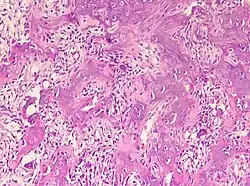

Sie bestehen aus einem stark gefäßversorgten „Kern“ (Nidus), der von einer rundlichen oder spindelförmigen Zone reaktiv wachsenden, verdichteten (sklerotischen) reifen Knochengewebes umgeben ist. Vorzugsweise sind Osteoid-Osteome in Ober- und Unterschenkelknochen lokalisiert. Überschreitet der Nidus eine Größe von 1,5 cm, wird die Veränderung als Osteoblastom bezeichnet.